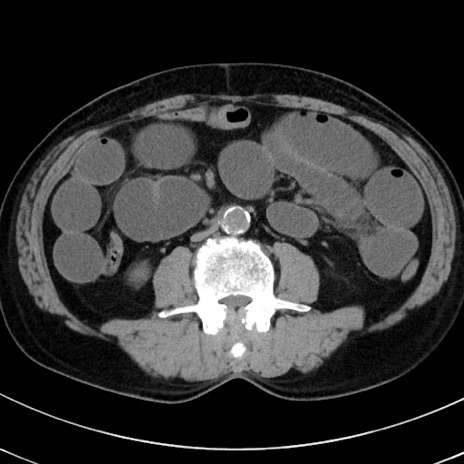

症例38(横断像)

【症例】70歳代 男性

【主訴】腹痛・嘔吐

【現病歴】昨晩より、嘔吐・腹痛あり。今朝になっても嘔吐あり。来院。

【既往歴】心臓バイパス手術、開腹胆摘、腸閉塞

【身体所見】BP 107/71mmHg、HR 116/min、腹部:平坦、軟、下腹部に軽度圧痛あり。反跳痛なし。

【データ】WBC 15100、CRP 0.32